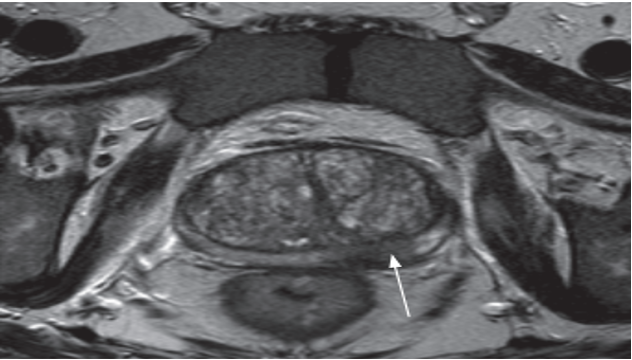

MRI

Becoming the preferred imaging modality for suspected prostate cancer and to demonstrate extracapsular tumour spread and possible lymph node metastases.

It is used to assess early stage prostate cancer in patients being considered for radical surgery or radiotherapy

Other indication: Clinical suspicion of prostate cancer despite negative transrectal ultrasound (TRUS) or TRUS-guided biopsy.

MRI of early prostate cancer. (a) T2-weighted MRI demonstrating focal low signal intensity in the left peripheral zone (arrow)